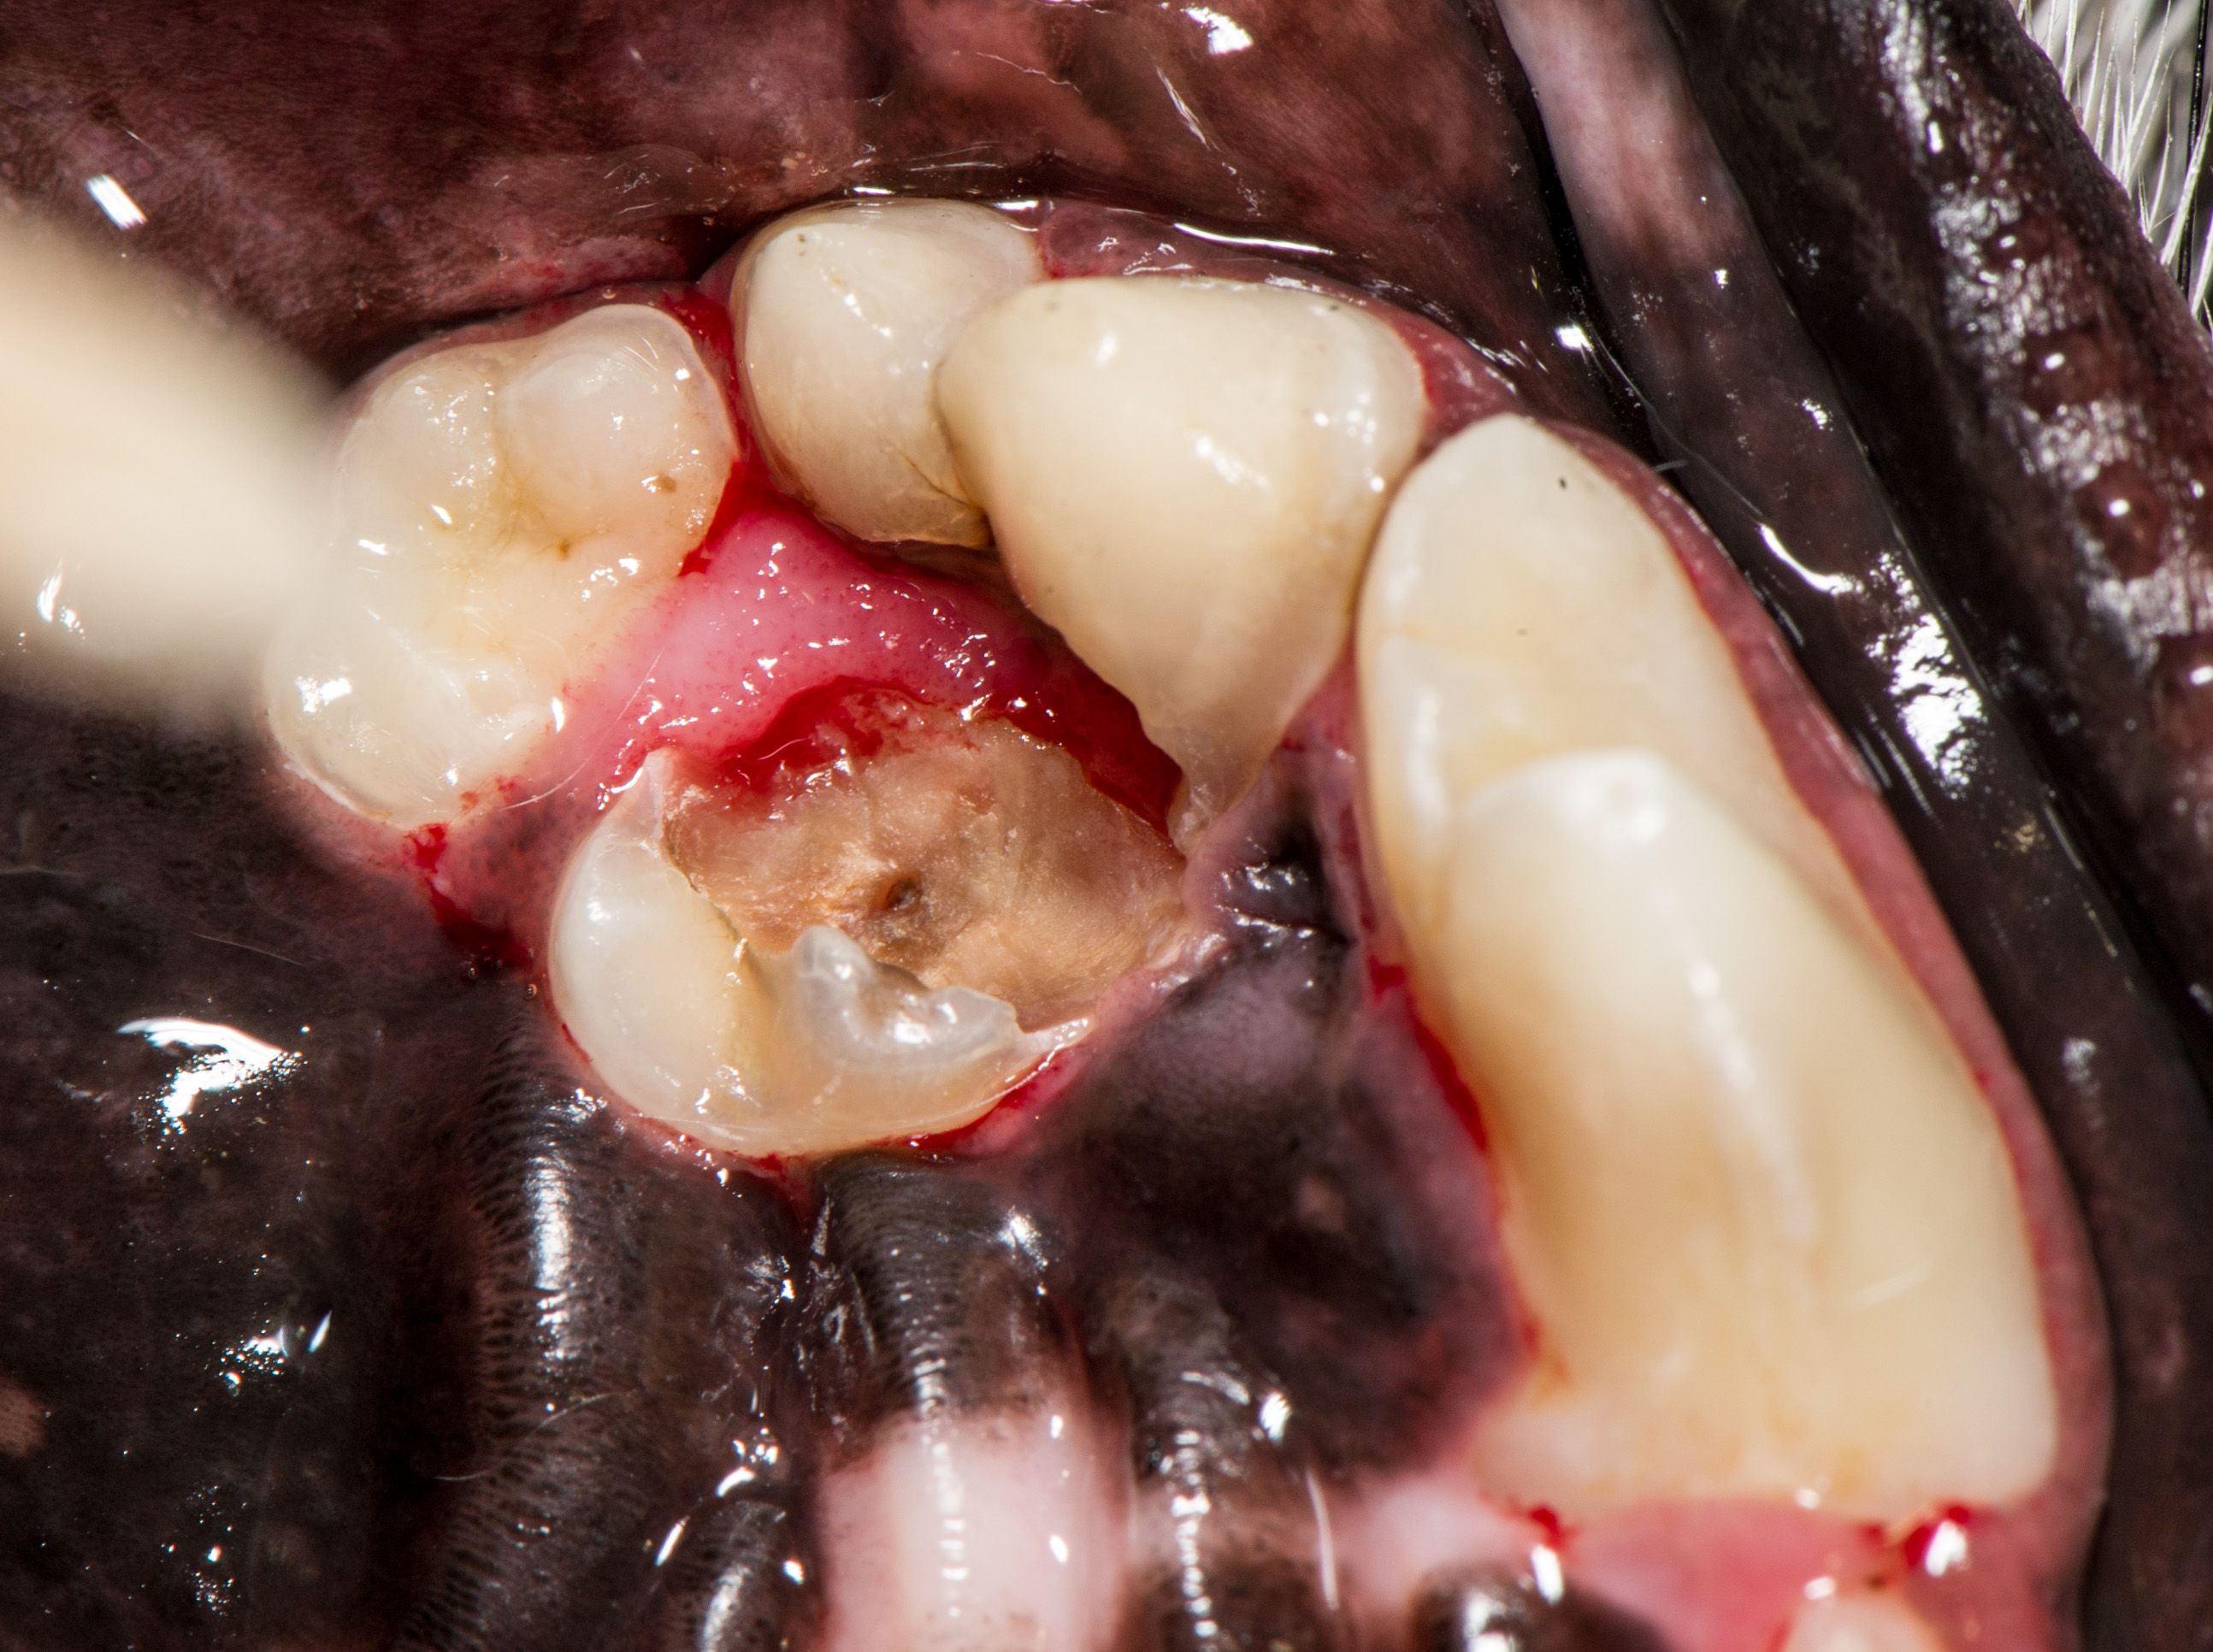

Dental caries in dog.